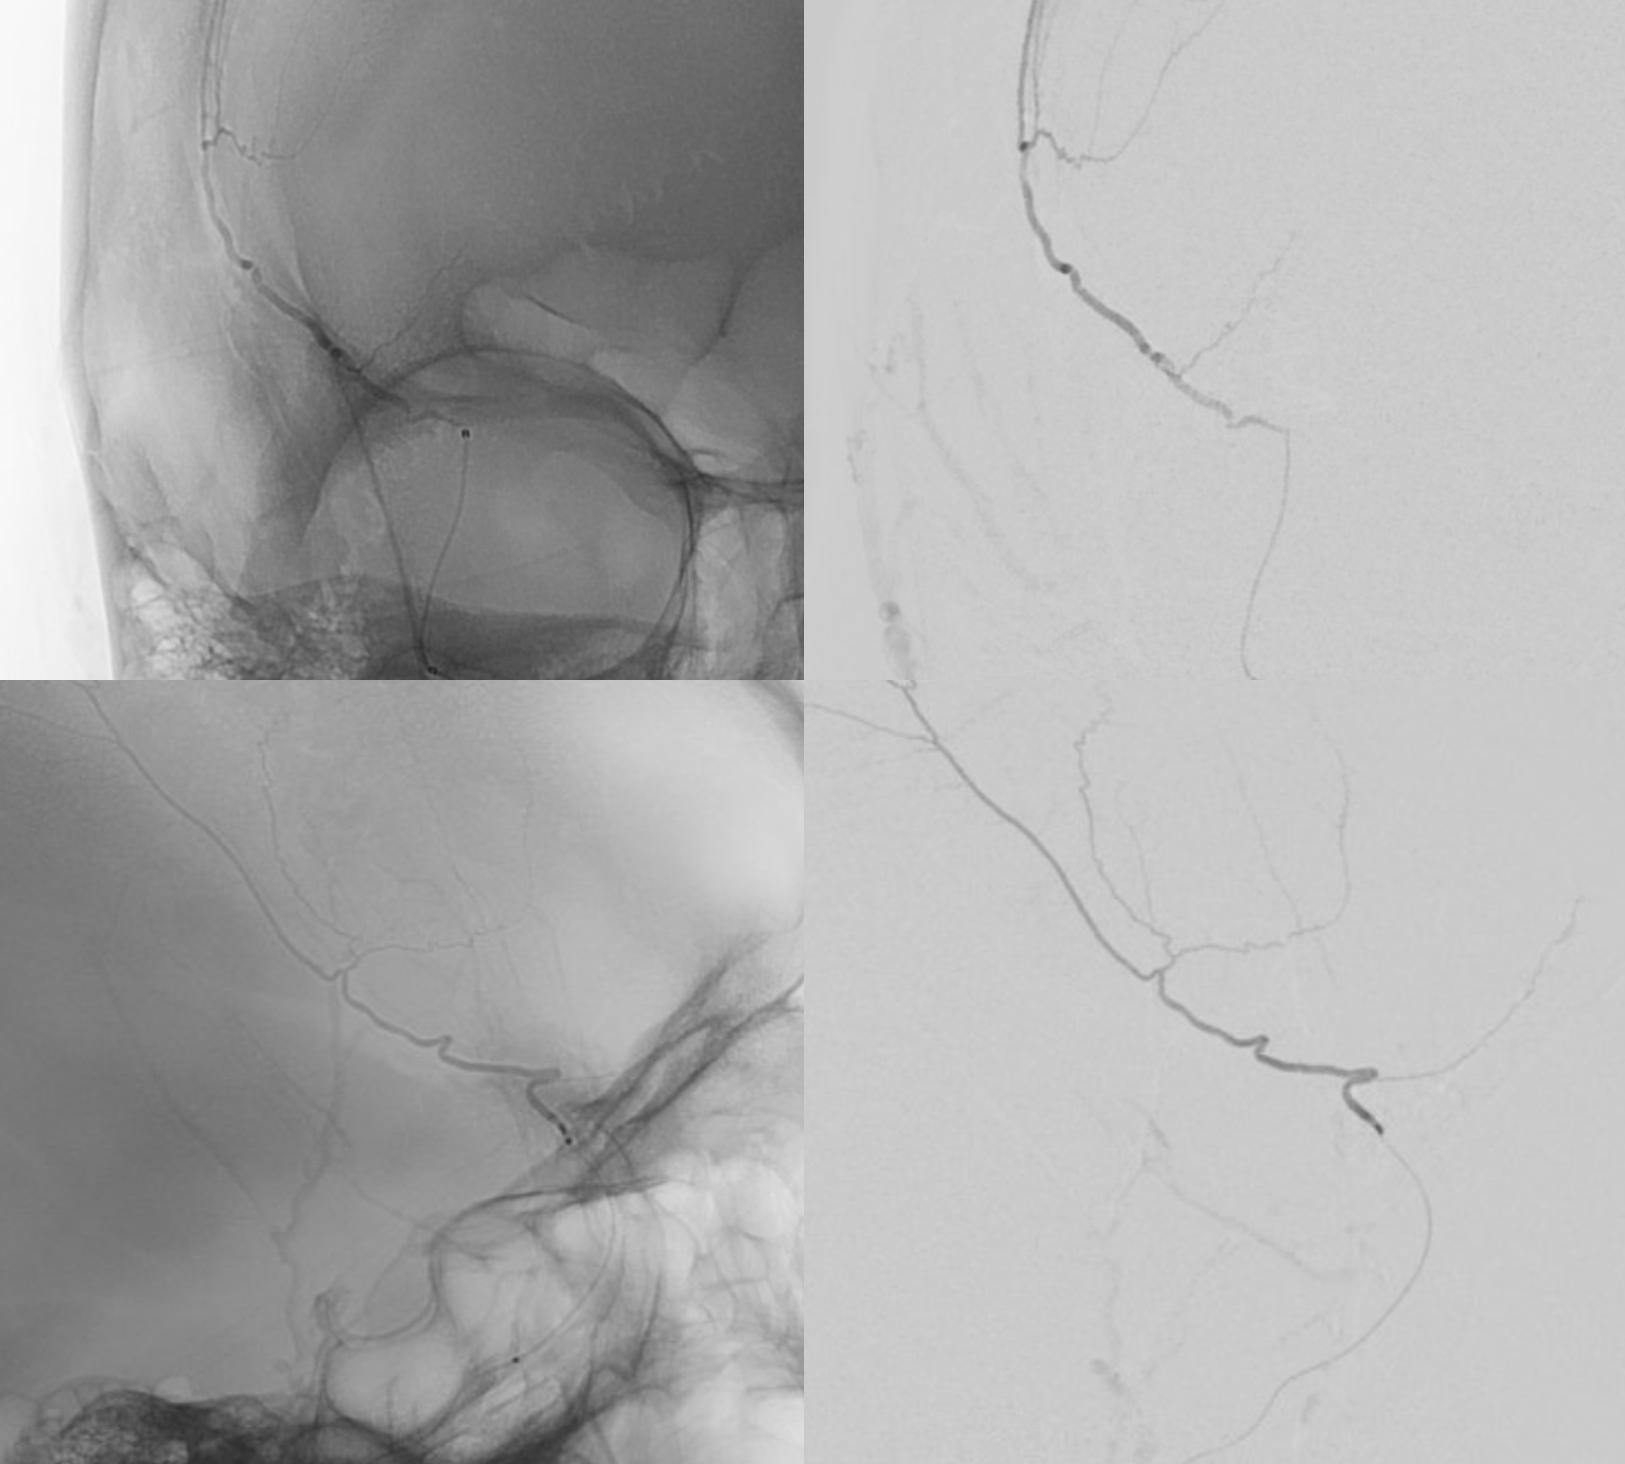

From neuroangio.org

Subdural Embolization Multiple Orbital Anastomoses nBCA Technique Wedge Position Pulmonaliskatheter After further insertion the pac will finally reach its wedge position. the major hemodynamic indices measured on pulmonary artery catheter (pac) are pulmonary artery and. the tip of the catheter lays into the main pulmonary artery, where the balloon can be inflated and deflated for. 2.3.4 wedge position. this video explains about the pulmonary artery catheter.. Wedge Position Pulmonaliskatheter.

Subdural Embolization Multiple Orbital Anastomoses nBCA Technique Wedge Position Pulmonaliskatheter when the balloon is inflated it measures pulmonary capillary wedge. this video explains about the pulmonary artery catheter. 2.3.4 wedge position. the major hemodynamic indices measured on pulmonary artery catheter (pac) are pulmonary artery and. After further insertion the pac will finally reach its wedge position. the tip of the catheter lays into the main. Wedge Position Pulmonaliskatheter.

Subdural Embolization Multiple Orbital Anastomoses nBCA Technique Wedge Position Pulmonaliskatheter when the balloon is inflated it measures pulmonary capillary wedge. the tip of the catheter lays into the main pulmonary artery, where the balloon can be inflated and deflated for. the major hemodynamic indices measured on pulmonary artery catheter (pac) are pulmonary artery and. 2.3.4 wedge position. After further insertion the pac will finally reach its. Wedge Position Pulmonaliskatheter.